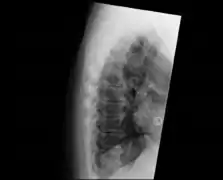

| DISH in an 80 year old female, also with T11 fracture. | |